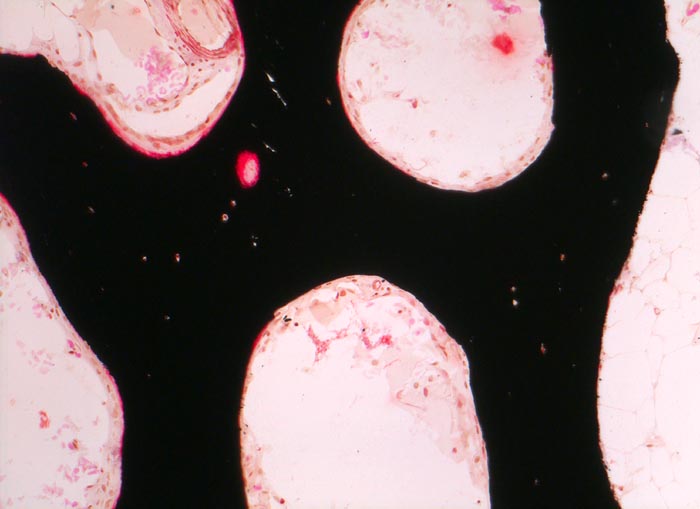

PathoPic ID 3508 - normales Osteoid

normales Osteoid

Knochenmark, Beckenkamm

Schmaler roter Osteoidsaum.

100